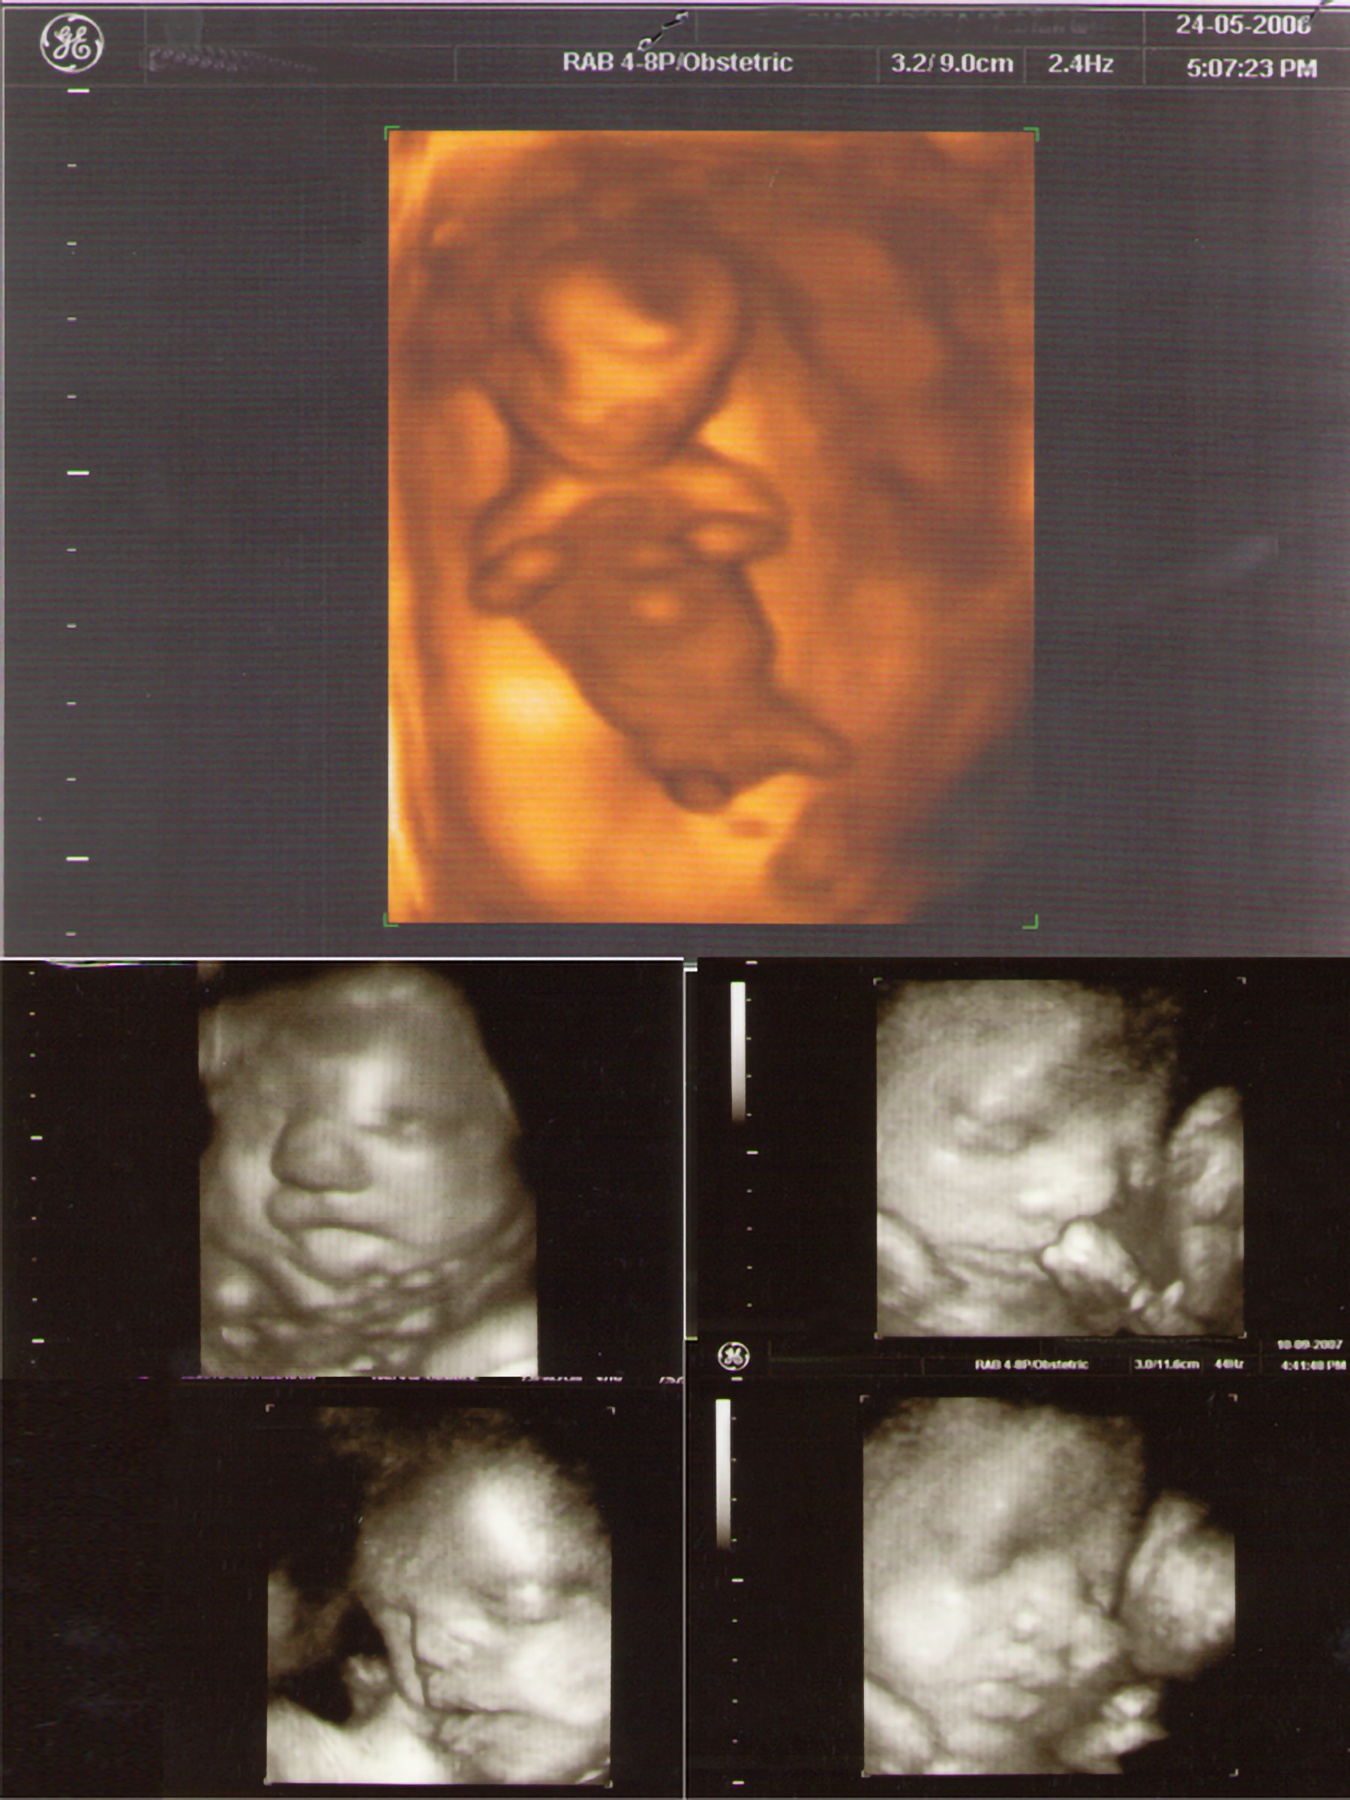

Gallery ECO